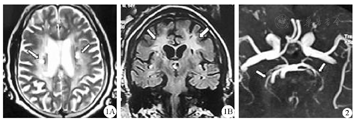

患者(先证者)男,54岁,因"左侧肢体无力、反应迟钝2年余,加重1年"来我院神经内科门诊。患者2年前无明显诱因出现左侧肢体无力,反应迟钝,言语含糊,走路向左侧偏斜。曾就诊当地医院,按"腔隙性脑梗死"给予对症处理,效果不佳。1年前,上述症状逐渐加重,且认知障碍加重。否认偏头痛、高血压、糖尿病、血管淀粉样变等病史,否认吸烟、饮酒史。体检:神志清,精神可,言语含糊,记忆力、计算力下降,颅神经检查无异常。左侧肌力3级、肌张力下降。四肢腱反射无异常,浅深感觉无异常,病理征(-),脑膜刺激征(-)。实验室检查结果:甘油三酯:2.41 mmol/L,同型半胱氨酸:16.11 μmol/L。双侧颈动脉超声未见明显异常。简易智能精神状态检查(MMSE)量表评分15分(<24分),提示认知功能受损。头颅MRI示:双侧额顶叶皮层下及桥脑多发缺血变性灶和软化灶,脑白质脱髓鞘改变(图1);SWI未见明确出血病灶;磁共振血管成像(MRA)示:动脉硬化(图2)。采用全外显子组测序发现NOTCH3基因第19号外显子存在一杂合错义突变(c.3043T>A),引起了第1015位的氨基酸由半胱氨酸变成了丝氨酸(图3)。诊断为CADASIL。

1A:矢状位T2WI,双侧侧脑室旁见对称晕状高信号(箭头所示);1B:冠状位T1 FLAIR,双侧额顶叶皮层下可见多个高信号(箭头所示);2:提示颅内动脉僵直,双侧大脑后动脉分支稀少(箭头所示)